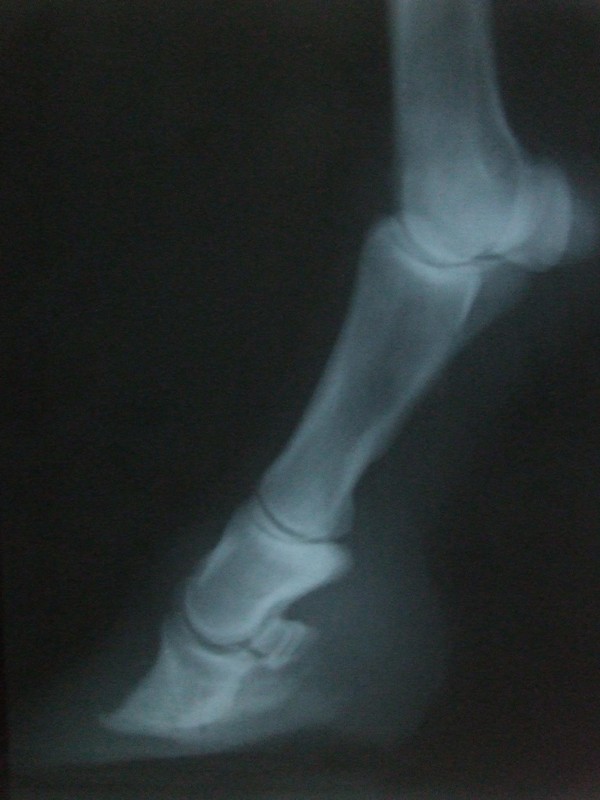

Levá přední 19.3.20009

levá přední